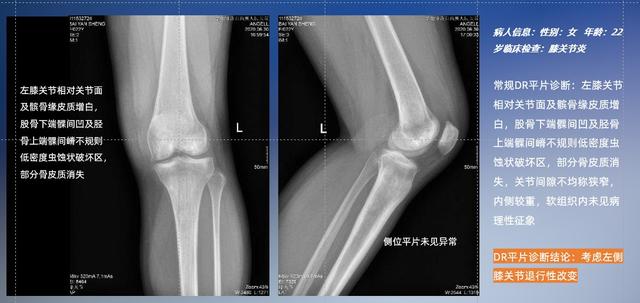

普通平片掃描與WR-3D掃描前后診斷結果對比

與此同時,數字化X線攝影技術相較于CTMRI來說,能快速獲取真實、直觀、滿足臨床需要的影像。DR的圖像具有圖像層次豐富、空間分辨力高、影像邊緣銳利清晰、密度分辨力高級細微結構表現出色等特點,針對膝關節解剖結構數字化X線攝影技術應用價值很高,尤其是是對骨小梁與骨皮質的顯示非常清楚。在負重位狀態下,數字化X線三維攝影掃描與重建,能夠更好的呈現受檢者關節受力改變的狀態。安健科技創新的WR-3D動態三維數字化X線攝影技術,通過數字化X線攝影完成三維掃描并重建三維影像信息,包括MPR多平面重建、MIP重建以及VR繪制。掃描時間短,劑量相較于CT設備大幅縮減,同時成本更低,在臨床診斷以及醫療方案制定中具有極大的價值意義。相較于普通平片下的負重位掃描,負重位動態三維掃描攝影技術能夠避免二維狀態下的組織結構重疊、密度分辨率不足、組織解剖結構難以分辨等問題,WR-3D支持多角度的動態三維攝影觀察,能全面的呈現被檢查部位在多個角度下三維影像信息,極大的減少了二維負重位檢查的漏診率。